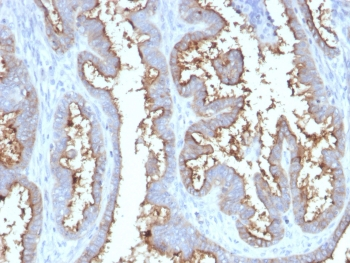

IHC staining of FFPE human tonsil tissue with CD73 antibody (clone NT5E/2545). HIER: boil tissue sections in pH9 10mM Tris with 1mM EDTA for 10-20 min and allow to cool before testing.

IHC staining of FFPE human tonsil tissue with CD73 antibody (clone NT5E/2545). HIER: boil tissue sections in pH9 10mM Tris with 1mM EDTA for 10-20 min and allow to cool before testing.